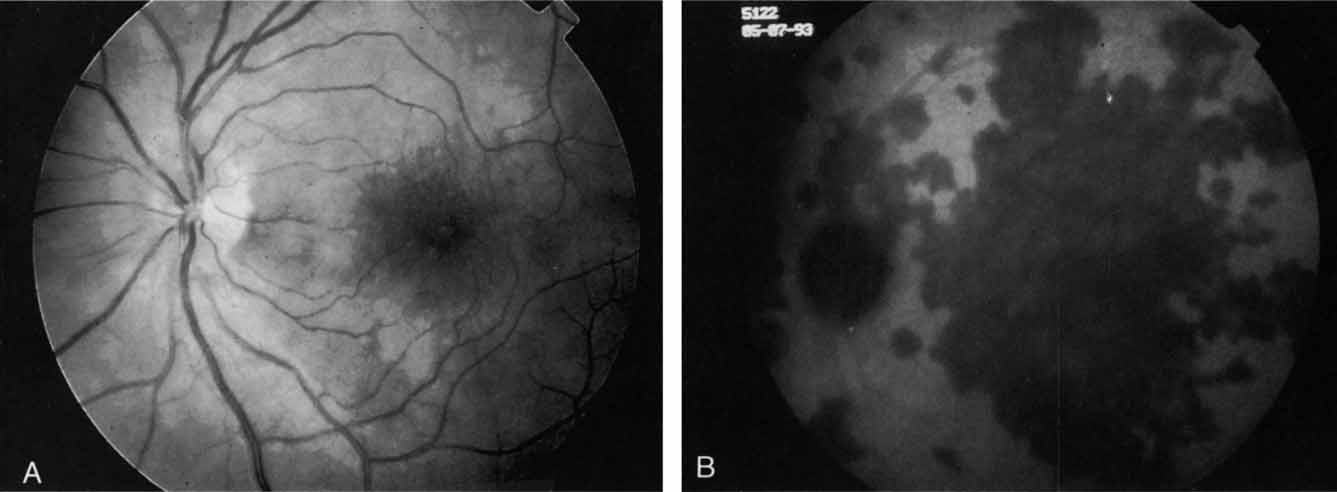

An important report by Chang and co-workers27 lends support to the rationale for interpreting the hyperfluorescence seen on ICG angiography as CNV. In this clinicopathologic study, a patient was identified who had experienced subretinal hemorrhage with early signs of occult CNV on fluorescein angiography (Fig. 4A). Fluorescein angiography demonstrated blocked fluorescence (Fig. 4B). The ICG study, however, demonstrated late staining in a well-circumscribed fashion, which the authors interpreted as a “plaque” of occult CNV (Fig. 4C). When the patient died, this area was evaluated and studied histopathologically and compared with the picture seen on ICG angiography. The area of hyperfluorescence on the ICG study corresponded precisely to a thin layer of fibrovascular tissue beneath the pigment epithelium and neurosensory retina, confirming that the late-staining tissue imaged with ICG angiography was truly a neovascular membrane (Fig. 4D).